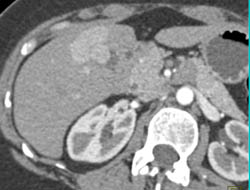

Focal Nodular Hyperplasia (FNH)